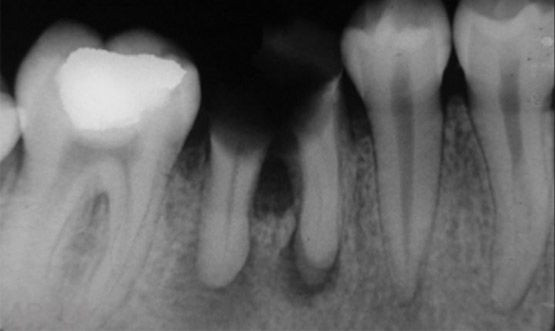

Radiografía dental

Las radiografías dentales son un tipo de imagen de los dientes y la boca. Los rayos X son una forma de radiación electromagnética de alta energía y penetran el cuerpo para formar una imagen en una película o en una pantalla. Las radiografías pueden tomarse de manera digital o en una película, son un método muy útil para identificar problemas dentales que no se perciben a simple vista.